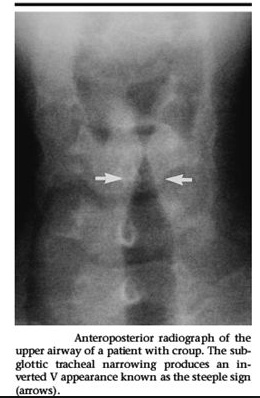

parainfluenza seal: Seal bark cough seen in Croup (caused by parainfluenza virus)

wind blowing in: Inspiratory stridor seen in Croup

church with steeple: Patients with Croup will often have a "steeple sign" on Chest X-ray, narrowing of subglottic region

aka laryngotrachealbronchitis.,